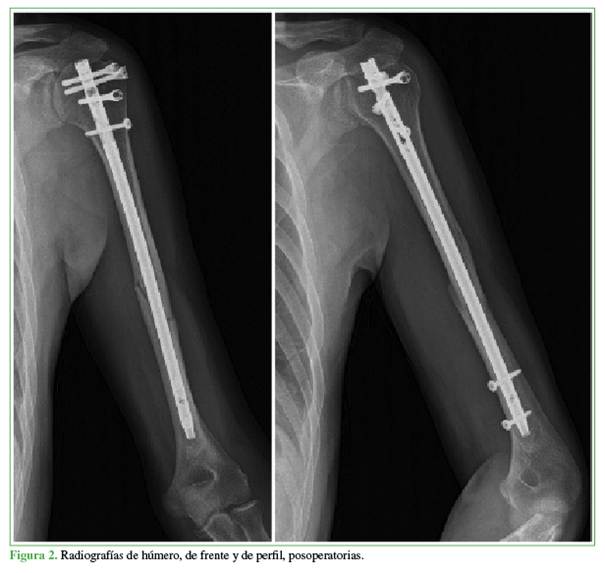

Todos los pacientes fueron tratados inicialmente con un cabestrillo de Vietnam por 2 semanas. Se indicaron movimientos de pronosupinación de muñeca y flexo-extensión de muñeca y codo a las 24 h de la cirugía. El movimiento pendular asistido por la extremidad sana se inició en la segunda semana. La movilidad activa del hombro comenzó en la tercera semana. Se permitió la actividad sin restricciones contra la gravedad 6 semanas después de la operación y se introdujeron actividades con carga de peso y ejercicio a las 12 semanas. El seguimiento clínico-radiográfico promedio fue de 18 meses (rango 12-24). Se realizaron controles radiográficos en el posoperatorio inmediato, a los 15 y 45 días, a los 3, 6, 12 y 18 meses (Figura 2).